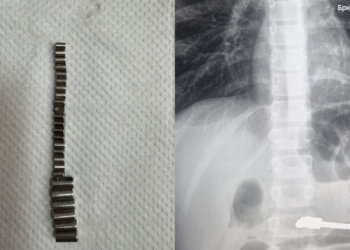

Фото: НДН.инфо